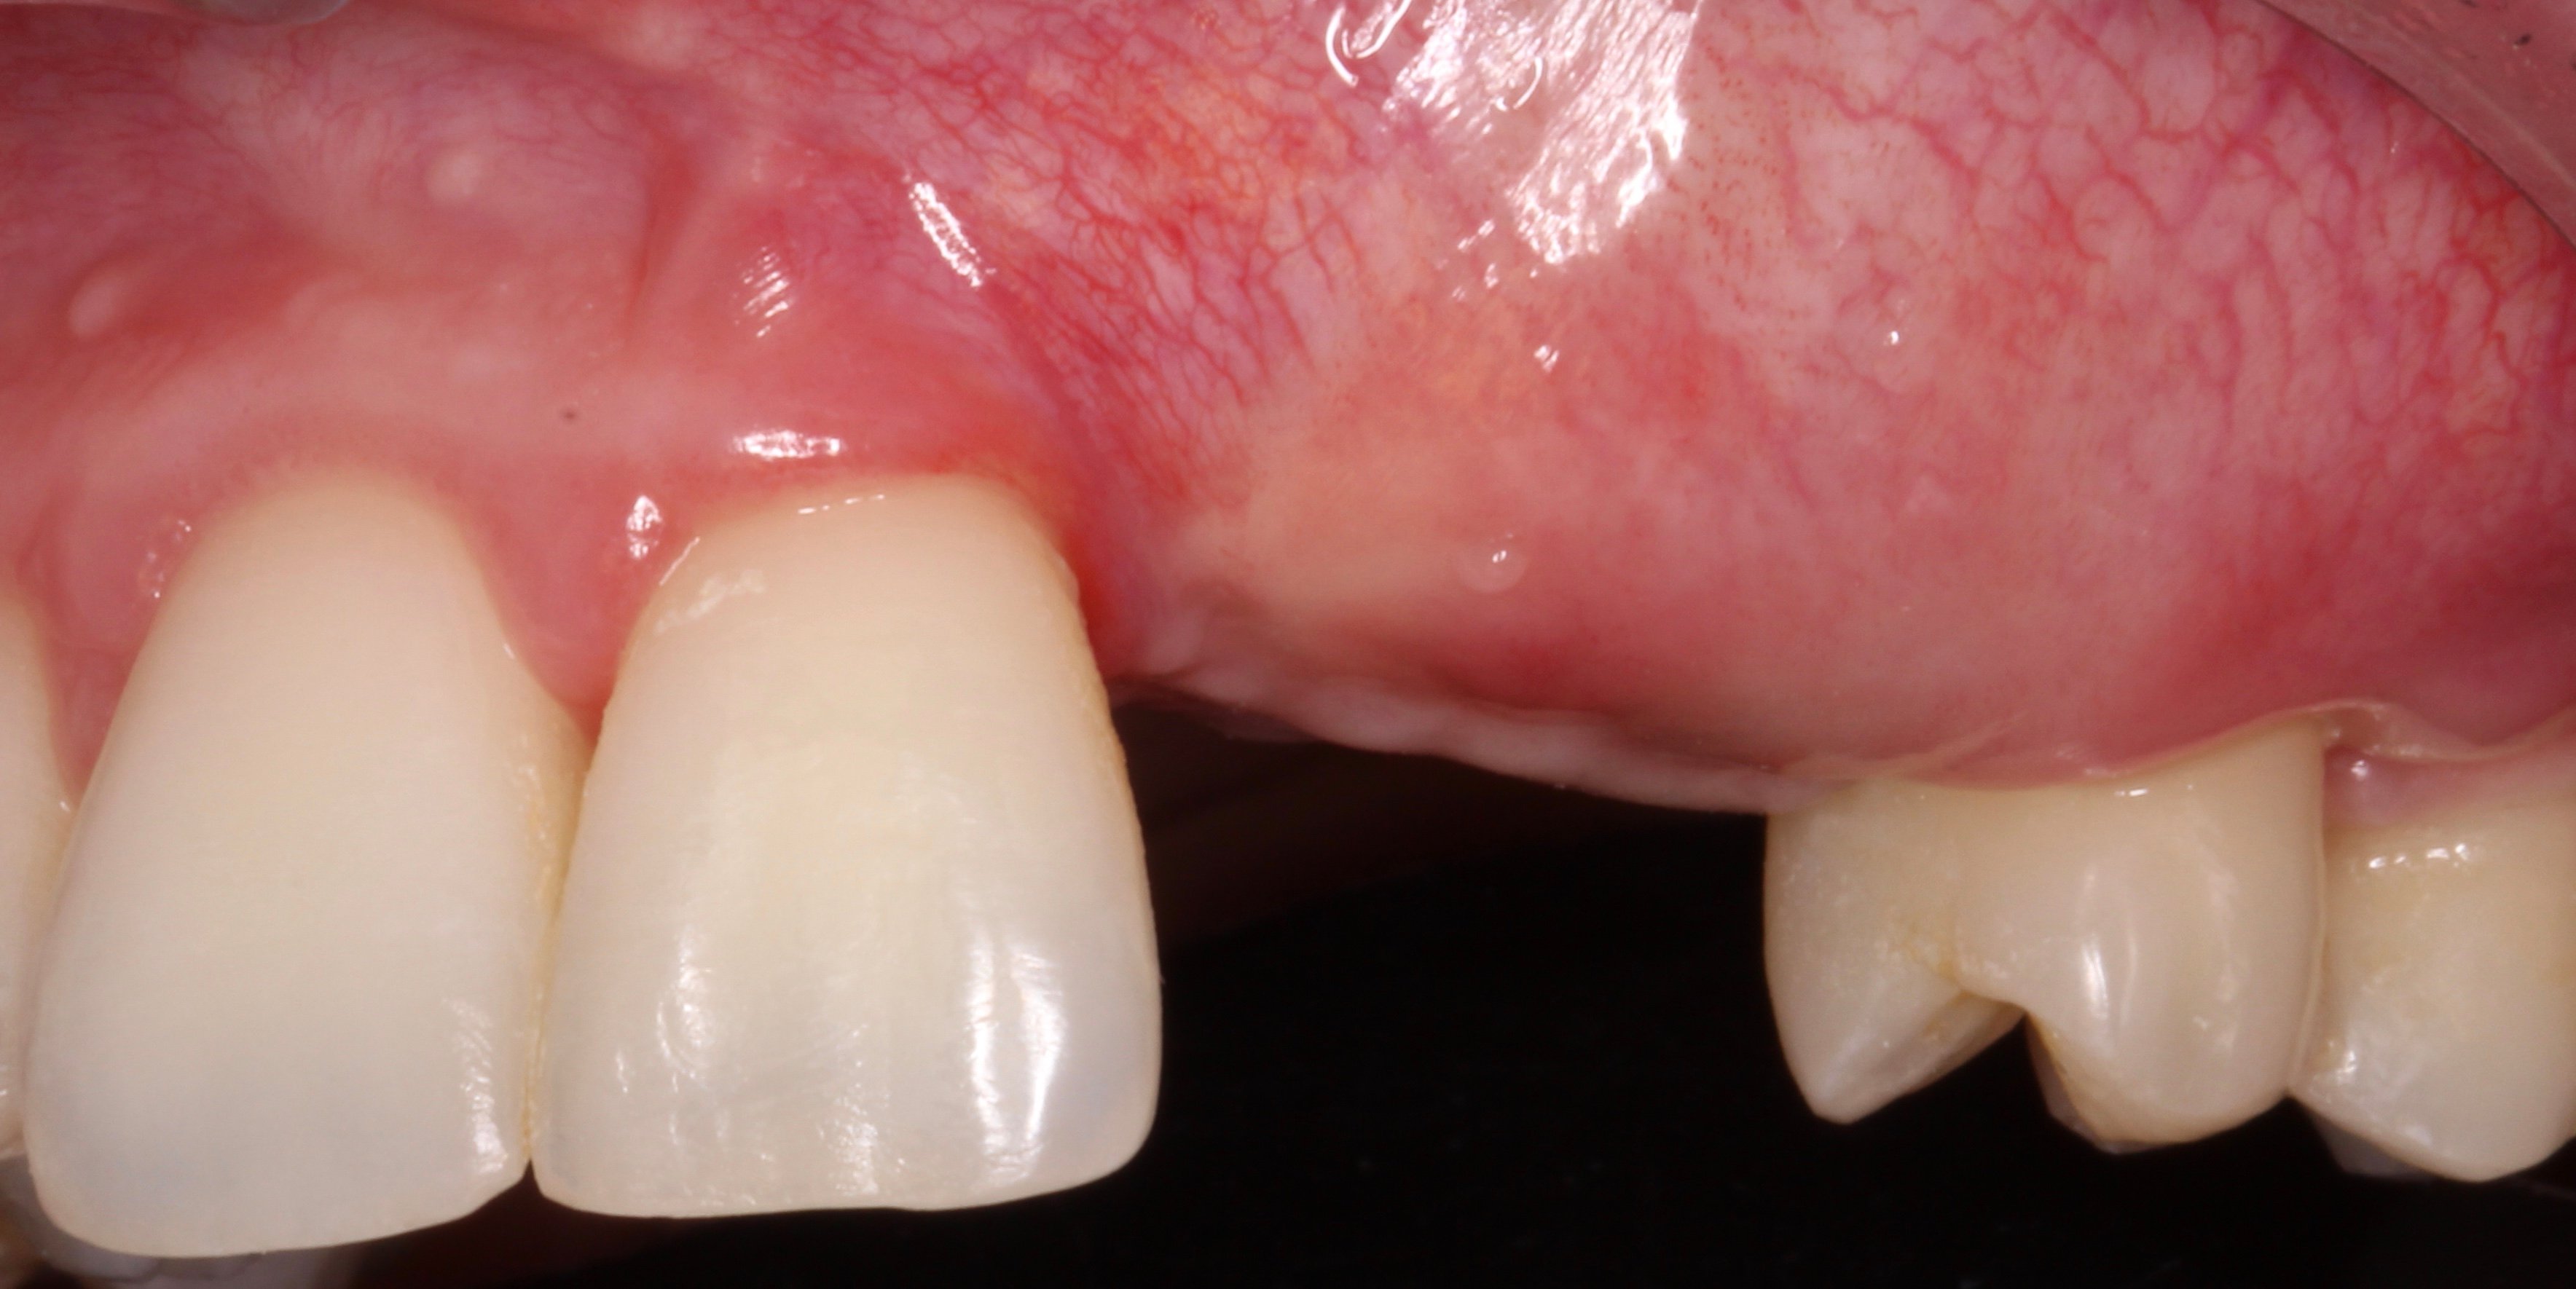

- 1 year later: Reentry and implant placement at 23 + connective tissue graft to solve the papilla loss at distal aspect of tooth 21.

- 2 months later: Free connective tissue to reposition the mucogingival line.